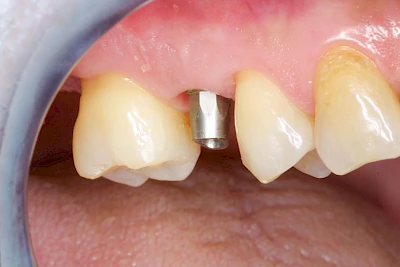

Implantate sind künstliche Zahnwurzeln. Nach einer gewissen Einheilzeit im Knochen (meist 3-6 Monate) erfolgt über einen separaten Aufbau (Abutment) die Befestigung einer Krone bzw. Brücke oder Zahnprothese.

Implantate: Bestandteile